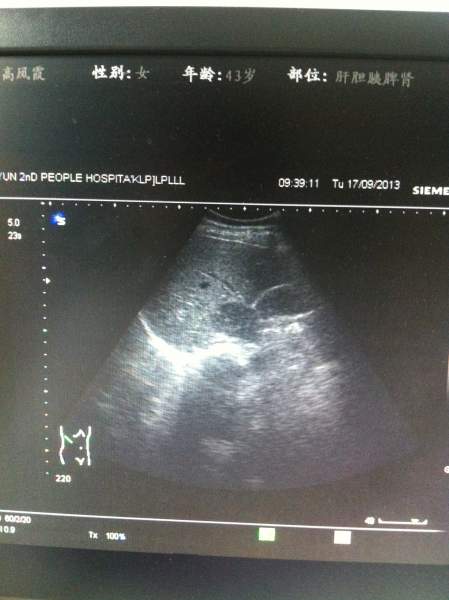

超声图像,各位大侠帮忙看下,肝上的这块是不是占位? 已有2人参与

患者今天前到我单位体检,两月前在另一单位体检过,结果正常,这次看肝上像有异常回声,让她再去上级单位复查,第二天患者去了,复查结果说是正常。 难道我们图像显示的是肝尾叶?回声可以这么低吗?看着还有边界的样子,难道是部分容积效应?真心很纠结,求指教,谢谢! IMG_1411.JPG IMG_1412.JPG IMG_1413.JPG IMG_1416.JPG |